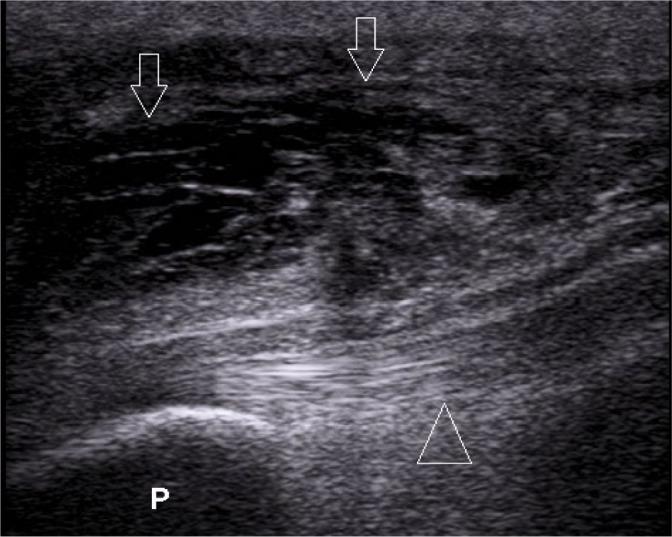

High-resolution ultrasonography has many advantages in the imaging of the musculoskeletal system, when compared to other imaging methods, particularly in superficial, easily accessible parts of the body. It is a perfect diagnostic tool for visualizing the most common pathologies of the musculoskeletal system, including the bursae. Inflammation of bursae is frequent, and it can mimic other diseases of the musculoskeletal system. Therefore, knowledge of normal ultrasound anatomy of the bursae, their exact location in the human body, and the sonographic signs of their most common pathologies is essential for establishing a quick and accurate diagnosis by ultrasound. Common conditions affecting bursae, leading to bursitis, include acute trauma, overuse syndromes, degenerative diseases, inflammatory conditions (rheumatoid arthritis, psoriatic arthritis, gout etc.), infections such as tuberculosis, synovial tumors and tumor-like conditions (pigmented villonodular synovitis, osteochondromatosis), and many more. This review article presents and explains ultrasound examples of the most frequent pathological conditions affecting bursae. Images include normal and pathological conditions of bursae around the shoulder joint, elbow, hip, knee, and ankle joint.

与其他成像方法相比,高分辨率超声在肌肉骨骼系统成像方面具有许多优势,尤其是在身体浅表、易于检查的部位。它是可视化肌肉骨骼系统最常见病变(包括滑囊)的理想诊断工具。滑囊炎很常见,且可能与肌肉骨骼系统的其他疾病相似。因此,了解滑囊的正常超声解剖结构、它们在人体中的准确位置以及其最常见病变的超声征象,对于通过超声快速准确地做出诊断至关重要。影响滑囊并导致滑囊炎的常见情况包括急性创伤、过度使用综合征、退行性疾病、炎症性疾病(类风湿性关节炎、银屑病关节炎、痛风等)、感染(如结核病)、滑膜肿瘤和肿瘤样病变(色素沉着绒毛结节性滑膜炎、骨软骨瘤病)等等。这篇综述文章展示并解释了影响滑囊的最常见病理状况的超声实例。图像包括肩关节、肘关节、髋关节、膝关节和踝关节周围滑囊的正常和病理状况。